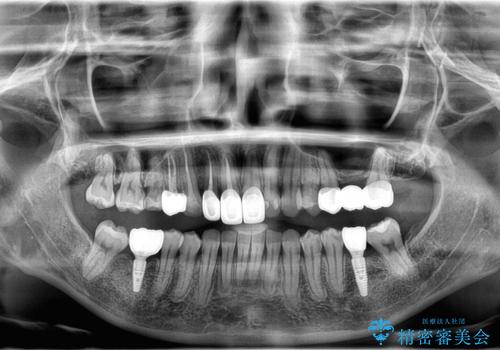

歯並びの改善とインプラントでのかみ合わせの回復 インプラント・セラミック・矯正全顎治療

- 歯医者が怖くて悪い歯をそのままにしてしまった、悪いところを治したいとのことで来院されました。

虫歯の歯や、歯を抜いてしまったところをそのまま放置していたことにより、歯並びも悪くなっていました。

矯正をはじめ、根の治療・インプラント・セラミックによる全体治療を提案させていただき、治療をしていくこととなりました。